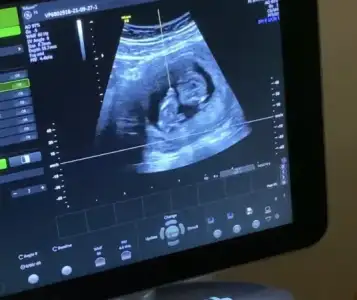

Erkek sankiKızlar 11+3 deyiz bize de tahminde bulunur musunuz

Emin olamadım başka USG varsa paylaşın 11 12 13 haftalar olmalıMerhaba rica etsem banada yorum yaparmısınızIkra meyra

Teşekkür ederim yarin kontrolüm var cinsiyeti öğrenirsem muhakkak haber edicem :) birsey sorabilir miyim nasil tahmin yaptiniz neye göre bilmiyorum bende cok merakıyım öğrenmek istiyorum.Erkek sanki